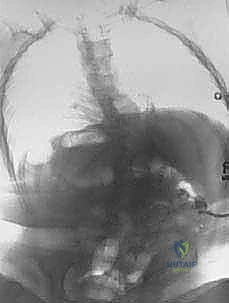

- التصوير الطبي المتقدم: يطلب الدكتور هطيف صور أشعة سينية بانورامية، أشعة مقطعية ثلاثية الأبعاد (3D CT Scan) لفهم التشريح العظمي المشوه، ورنين مغناطيسي (MRI) لتقييم الحبل الشوكي والتأكد من عدم وجود "الحبل الشوكي المربوط" (Tethered Cord).

المرحلة الثانية: الإجراء الجراحي خطوة بخطوة

- التخدير وتجهيز المريض: يتم تخدير الطفل بعناية فائقة، ووضعه على طاولة العمليات بوضعية تحمي الأعضاء الداخلية.

- الشق الجراحي والتعامل مع الأنسجة: يتم فتح الجلد بحذر شديد. في كثير من الأحيان، يتم استئصال الأنسجة الندبية القديمة. يستخدم الدكتور هطيف تقنيات الجراحة المجهرية (Microsurgery) للتعامل مع الأنسجة العصبية الرقيقة وتجنب تسرب السائل النخاعي.

- استئصال الفقرات (The Kyphectomy): هذه هي الخطوة الأكثر حساسية. يقوم الدكتور هطيف بتحديد الفقرات التي تشكل قمة الانحناء (عادة من 1 إلى 3 فقرات). يتم استئصال جسم هذه الفقرات بالكامل مع الأقراص الغضروفية المحيطة بها.

- تصحيح التشوه (Closing the Wedge): بعد إزالة الفقرات، يصبح العمود الفقري مرناً في تلك النقطة. بمهارة فائقة، يقوم الدكتور هطيف بضم الجزأين العلوي والسفلي من العمود الفقري معًا، مما يلغي الانحناء ويستعيد استقامة الظهر.

- التثبيت الميكانيكي (Spinal Fixation): للحفاظ على هذا التصحيح، تُستخدم براغي وأعمدة معدنية مخصصة للأطفال. يتأكد الدكتور هطيف من تثبيت هذه الأدوات بقوة في الحوض والفقرات السليمة لضمان ديمومة النتيجة.

- الترقيع العظمي (Bone Grafting): يتم وضع طعوم عظمية (غالباً من العظام التي تم استئصالها) حول منطقة الجراحة لتحفيز التحام العمود الفقري بيولوجياً لتكوين كتلة عظمية صلبة واحدة.